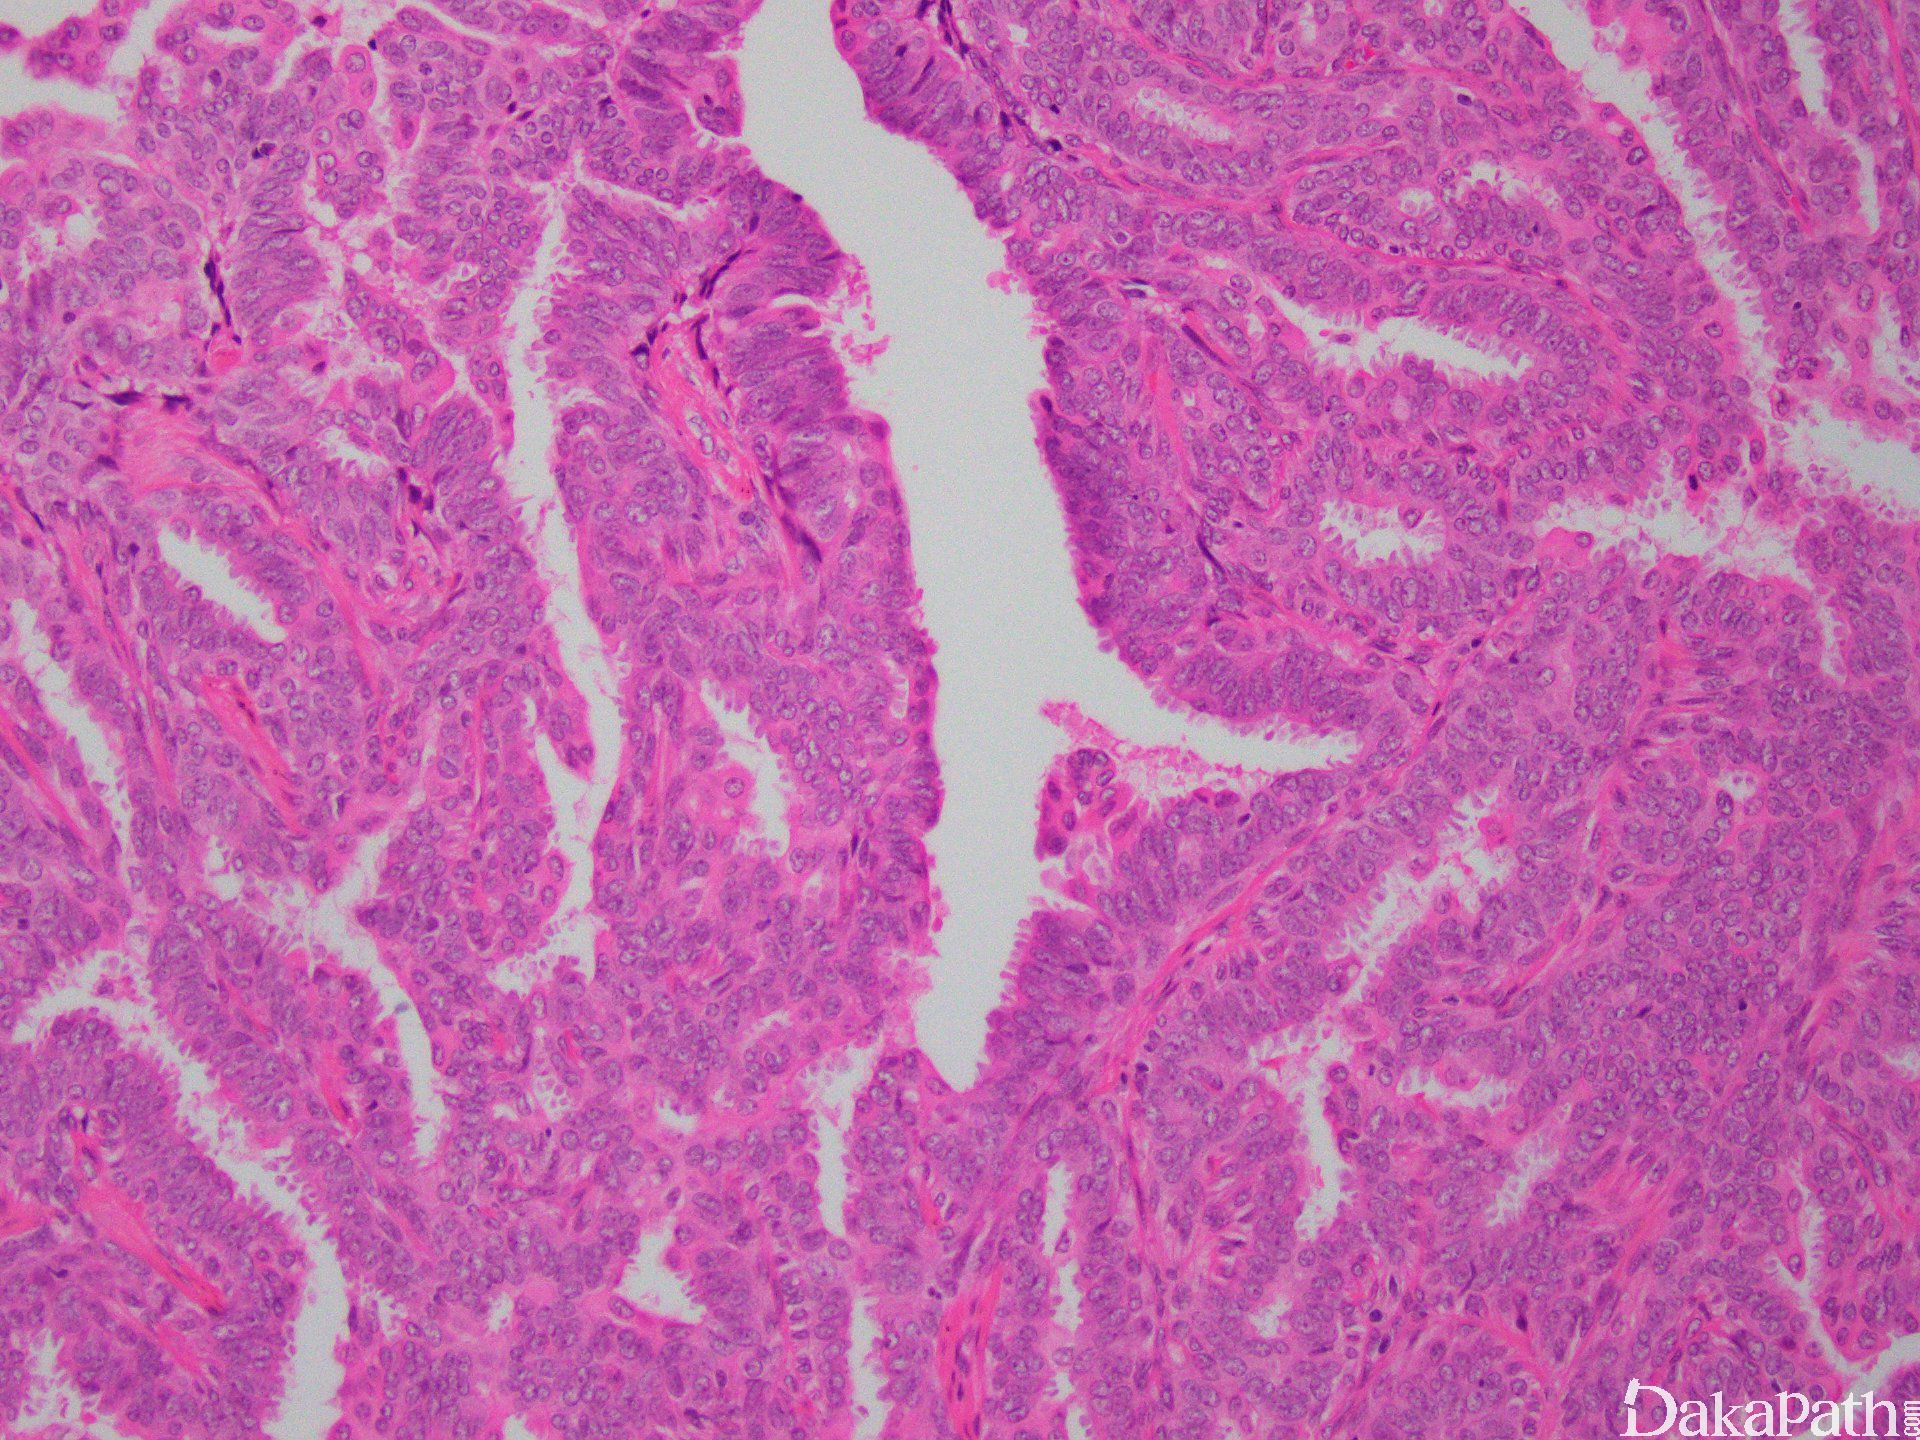

- 低倍镜显示界限清楚的导管内或囊内乳头状增生结节;

- 乳头纤维血管轴心覆以两种细胞,排列于乳头状结构面向管腔面的上皮细胞和位于上皮细胞和基底膜之间的肌上皮细胞;

- 上皮细胞可为一层或多层,立方形或柱状。肌上皮细胞立方或长轴平行于基底膜的短梭形,胞浆透亮,也可以增生,呈多层;

- 上皮细胞增生明显时,相邻乳头之间的上皮细胞相互连接,低倍镜下乳头结构模糊不清,但高倍镜下可见纤维血管轴心;

- 上皮细胞增生区域细胞呈流水样或螺旋状分布,胞质边界可形成不规则缝隙,这些特征均提示良性增生;